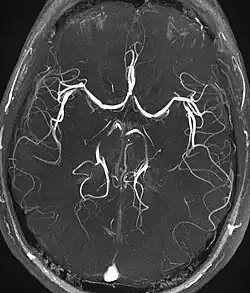

Magnetic resonance angiography

Magnetic resonance angiography (MRA) generates pictures of the arteries to evaluate them for stenosis (abnormal narrowing) or aneurysms (vessel wall dilatations, at risk of rupture). MRA is often used to evaluate the arteries of the neck and brain, the thoracic and abdominal aorta, the renal arteries, and the legs (called a "run-off"). A variety of techniques can be used to generate the pictures, such as administration of a paramagnetic contrast agent (gadolinium) or using a technique known as "flow-related enhancement" (e.g., 2D and 3D time-of-flight sequences), where most of the signal on an image is due to blood that recently moved into that plane (see also FLASH MRI).[39]

Techniques involving phase accumulation (known as phase contrast angiography) can also be used to generate flow velocity maps easily and accurately. Magnetic resonance venography (MRV) is a similar procedure that is used to image veins. In this method, the tissue is now excited inferiorly, while the signal is gathered in the plane immediately superior to the excitation plane—thus imaging the venous blood that recently moved from the excited plane.[40]